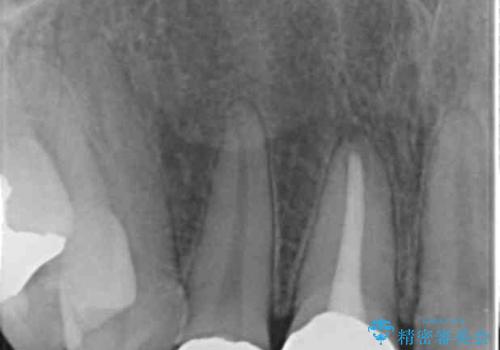

右上1番は、根の治療のやり直しをしています。

- 63.8万円(右上4~左上2:emaxクラウン 7万円x6本、仮歯 1万円x6本、歯周外科手術 15万円、右上1:精密根管再治療 9万円およびファイバーコア2万円)費用は治療当時の料金となります